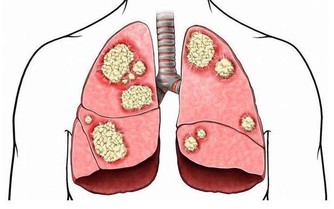

5、皮膚瘙癢終末期的腎病患者,由於體內的尿素不能經尿液排出,會通過皮膚排泄,由此刺激皮膚;

另外,身體內積累的毒素會導致周圍神經病變,也會引起皮膚瘙癢。